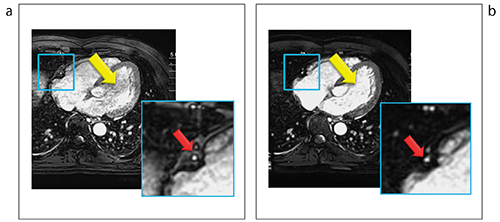

図3 血液信号の安定化と脂肪抑制改善の効果

a:従来法

b:新法

同被検者における比較。→は,右冠動脈周囲の脂肪信号,→は心腔内の血液信号を示す。新法(b)において血液信号の安定化,脂肪信号の抑制において改善効果が得られた。